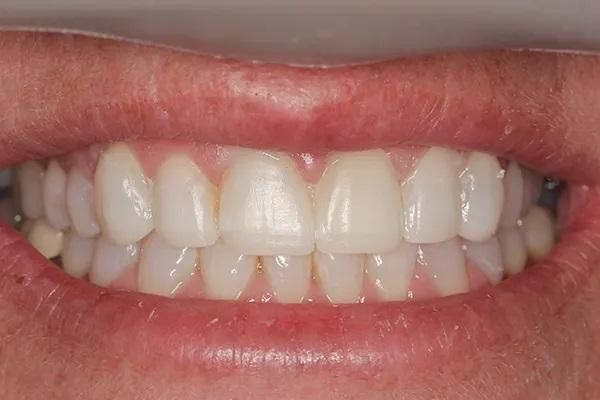

Для постоянной фиксации виниров использовался полупрозрачный цемент (RelyX Veneer Cement, 3M Oral Care) виниры были зафиксированы парами начиная с области центральных резцов, затем латеральные резцы и заканчивая клыками. Каждую реставрацию закрепляли с помощью 3-секундного светового отверждения, а излишки цемента удаляли с помощью ультразвукового скеллера. Окончательное отверждение осуществлялось путем полимерезации светом в течение дополнительных 20 секунд на каждый зуб. Результаты проведённого лечения показаны на фото с 9 по 12. Изменение улыбки пациентки с фиксированными постоянными реставрациями (фото 9). Демонстрация смыкания после лечения (фото 10). Портретная фотография анфас с широкой улыбкой (фото 11). Прицельные снимки зубов пациентки после проведенного лечения (фото 12).

Фото 10